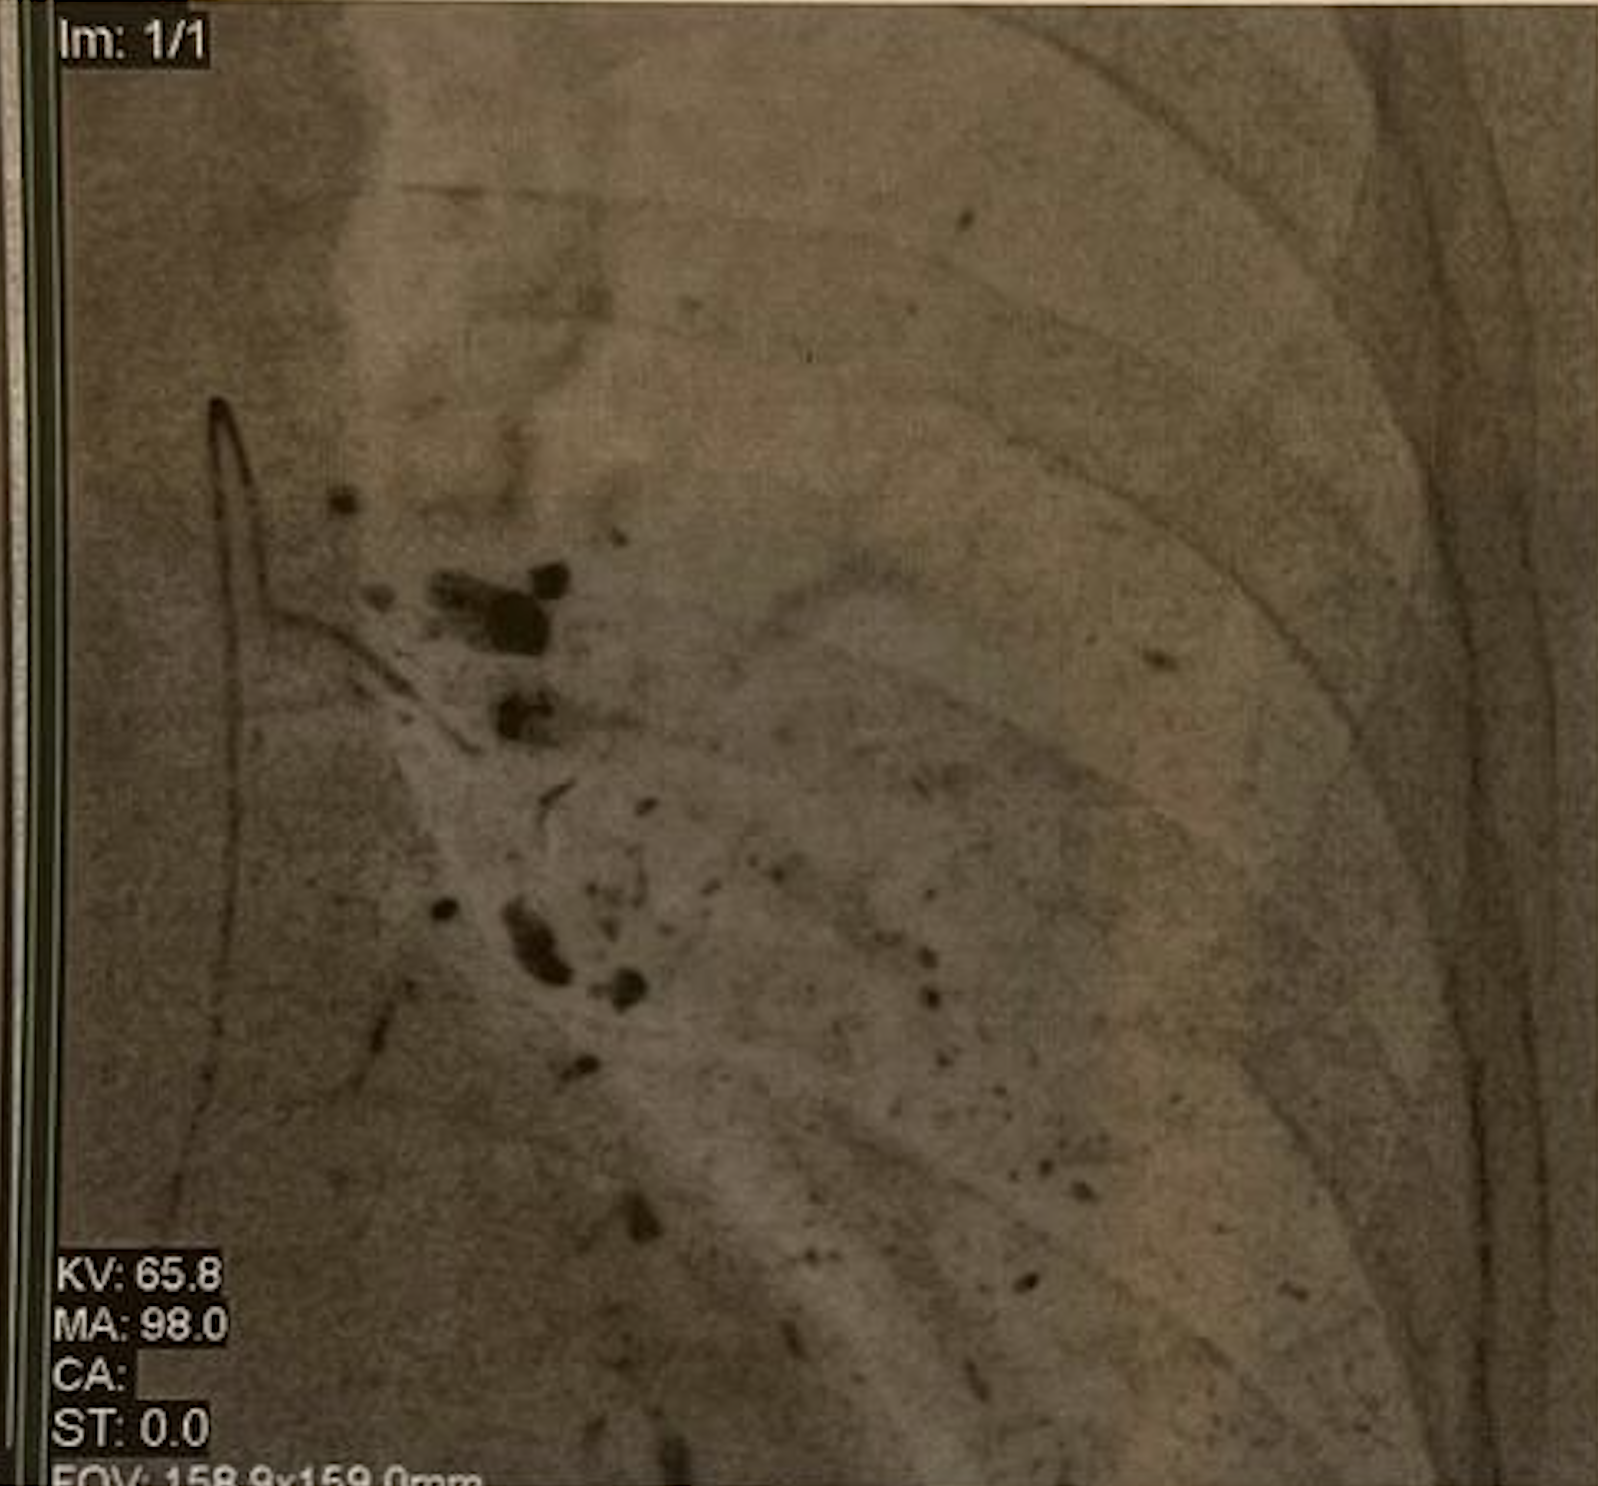

The new medical plan focused on a highly specialized, localized approach known as thoracic chemoembolization, or TPCE. Instead of relying on a single method, Mr. Jesus and his medical team decided to tackle the lung metastases from two different, complementary angles.

Bridging Care Between Spain & Germany

The treatment strategy required incredible coordination between his home in Spain and his new specialists in Frankfurt. Under the care of Prof. Vogl, the patient underwent a total of four TPCE sessions. This innovative procedure delivers targeted medication directly to affected lung areas, maximizing tumor impact while minimizing systemic side effects. To make the process as gentle on his body as possible, the four sessions were split into two separate arrivals. He completed the first two sessions in May 2025, rested for a month, and returned for the final two sessions in June 2025.